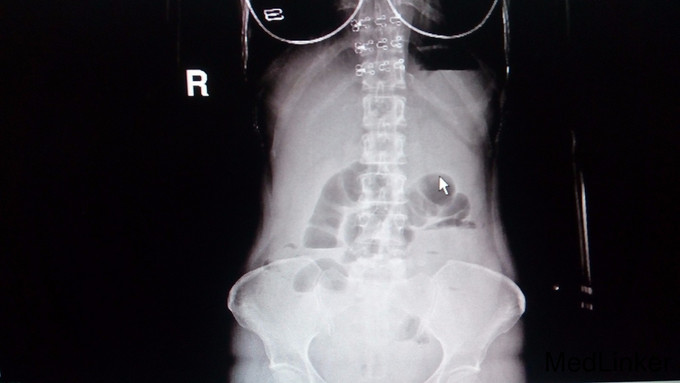

查体:腹部膨隆,脐下长约10cm手术疤痕,腹肌紧张,肠鸣音活跃。 辅助检查:超敏C蛋白50.7mg/L,白细胞13.27G/L,腹部立位平片提示中腹部肠管扩张,见多个气液平,肠梗阻。

诊断:粘连性肠梗阻 处理:明确无手术禁忌症后,全麻下行剖腹探查术,术中见肠粘连,小肠梗阻,行肠粘连松解术+病变部位肠切除术+肠吻合术。术程顺利,术后予补液、抗感染、营养支持等对症治疗。术后复查立位平片提示腹腔内积气肠管明显减少。